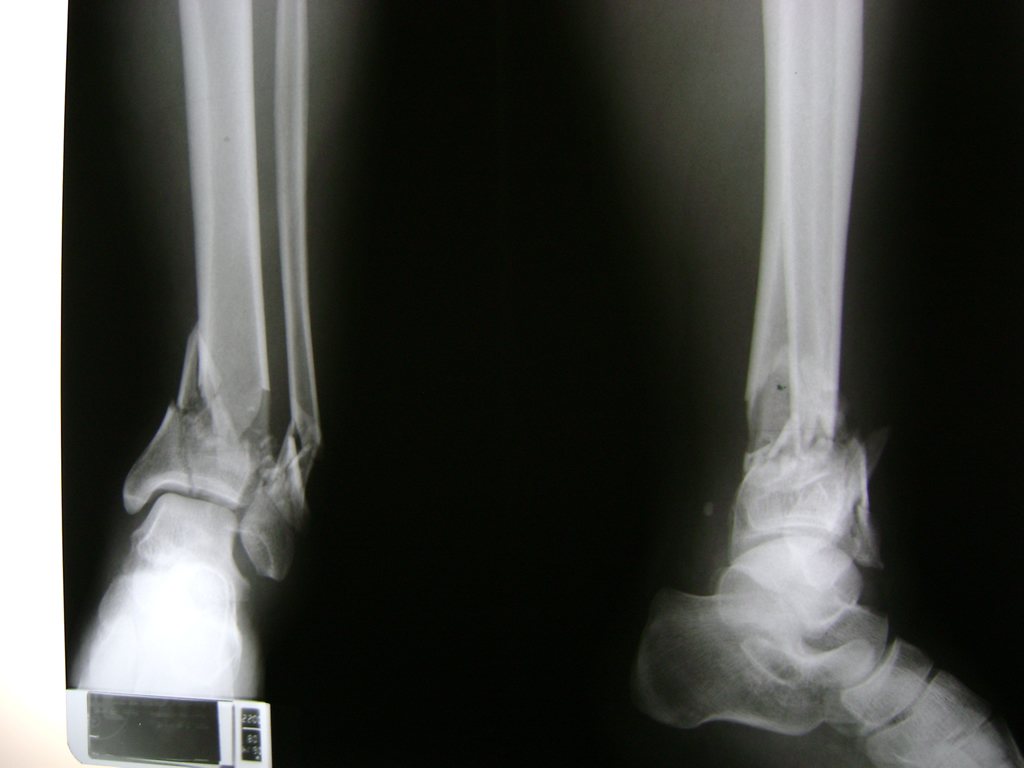

Una fractura de tobillo es la rotura de uno o más de los huesos del tobillo. Estas fracturas pueden ser:

- Parciales (el hueso está sólo parcialmente fisurado, no del todo).

- Completas (el hueso está perforado y está en 2 partes).

- Producirse en uno o ambos lados del tobillo.

Algunas fracturas de tobillo pueden requerir cirugía si:

- Los extremos de los huesos están desalineados entre sí (desplazados).

- La fractura se extiende hasta la articulación del tobillo (fractura intra-articular).